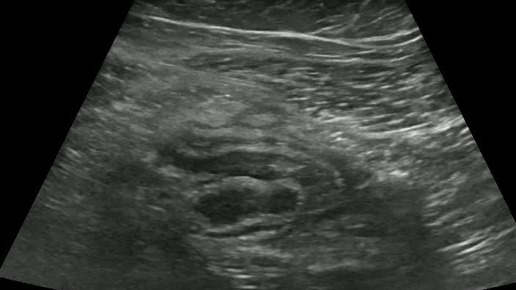

Ультразвуковые находки от врача УЗД Зорина Я.П.